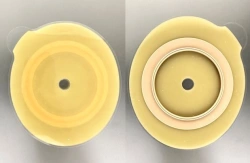

Medical product is intended for use in colostomies, ileostomies and urostomies for hermetic and secure attachment of stoma bags to the skin of the anterior abdominal wall, as well as to protect the skin of the peristomal area from stoma secretions and preserve the physiological functions of the skin due to the absorption of natural skin moisture (sweat, sebum).